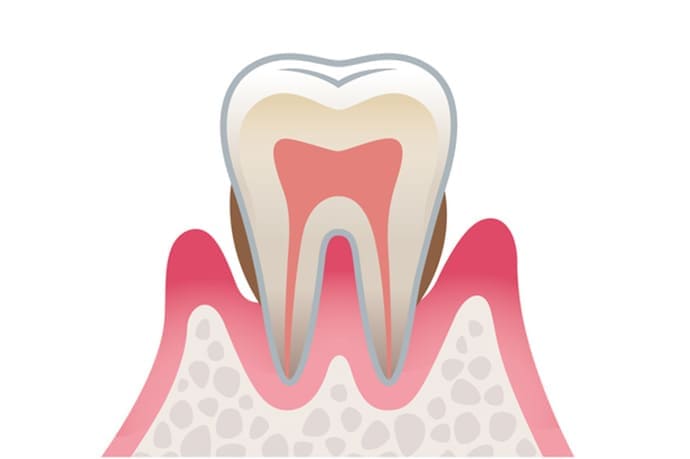

軽度歯周炎 危険度★★

軽度の歯周炎は歯茎が少し赤みを帯び腫れた状態になります。

軽度歯周炎の場合の目安は歯周ポケットが3~4mm程度と言われています。

この段階での治療法は、プラークや歯垢をスケーリングなどで取り除き、正しいブラッシングを毎日することです。